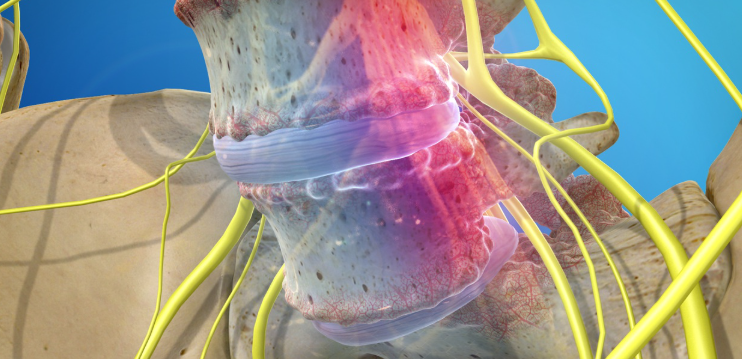

2. 신경 압박의 영향

척추 전방전위증의 진행이 심하면 척추관이 좁아지면서 좌골신경통 같은 신경성 통증이 동반되기도 합니다. 이는 단순히 허리 근육 문제를 넘어선 신경적 불편함으로 이어질 수 있어 조기 관리가 중요합니다.